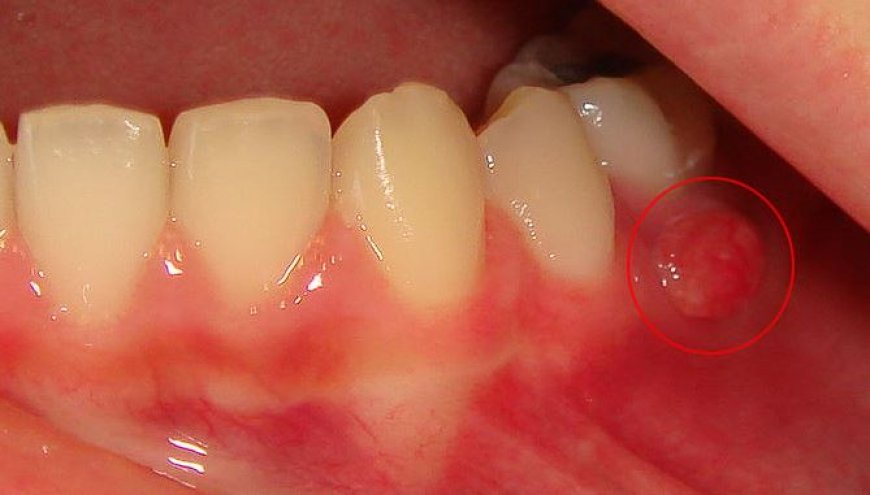

Diş apsesi, diş kökünde veya diş etinde oluşan, ağrı ve rahatsızlığa neden olan bir iltihaplanmadır. Bu iltihaplanma, bakterilerin diş pulpasına (dişin sinir ve kan damarlarını içeren yumuşak doku) girmesi ve burada bir enfeksiyon oluşturması sonucu oluşur. Diş apsesi, diş ağrısının en yaygın nedenlerinden biridir ve acil tedavi gerektiren ciddi bir durumdur.

Diş Apsesi Belirtileri:

• Diş apsesinin en belirgin belirtisi şiddetli diş ağrısıdır. Ağrı, genellikle gece veya dinlenme sırasında daha da kötüleşir. Diş apsesinin diğer belirtileri şunlardır:

• Diş etlerinde şişlik ve kızarıklık

• Yüzde şişlik

• Dişten irin gelmesi